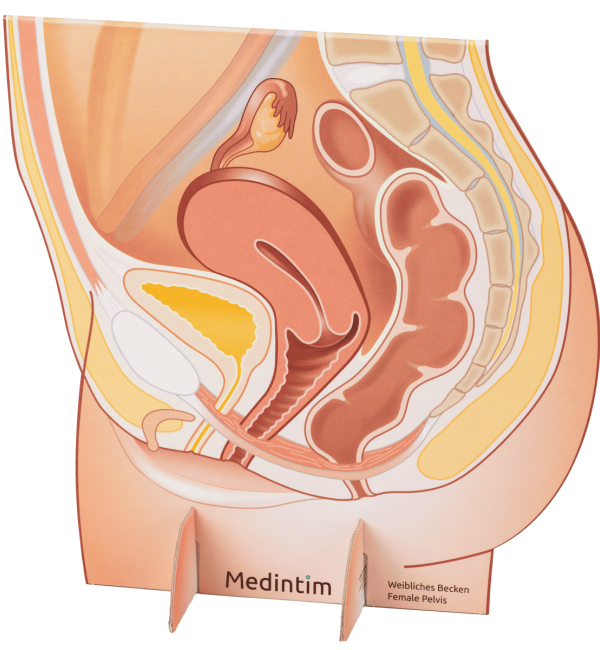

- Dispareunia

- Vaginite

- Annessite

- Stenosi vaginale

- Endometriosi

- Vaginismo

- Cicatrizzazione dopo episiotomia o lacerazione perineale

- Dopo interventi chirurgici ginecologici (per es. interventi per prolasso o in caso di tumori)

- Durante e dopo radioterapia/chemioterapia

- Dopo interventi di riduzione della vagina e formazione di cicatrici

- Malattie cutanee come determinate forme di lichen, per es. lichen sclerosus

- Vaginoplastica stretta (verginità) descritta come disturbo sessuale dall’interessata

Gli esercizi di dilatazione con il dilatatore Vagiwell sono opportuni anche quando le visite ginecologiche o l’uso di assorbenti interni sono molto dolorosi.